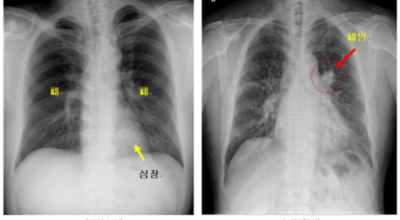

폐암 검사는 X-ray를 통해서 검사하는데 , 크기가 작거나 구석에 위치한 경우 확인이 어려운 경우도 있습니다. 그리고 조직 검사를 통해서 정확한 진단을 하게 되어요. 폐암이 발견되면 종양의 크기나 전이 여부 , 위치에 따라서 수술 여부를 결정하게 돼요.

수술 치료

악성 종양이 있는 폐의 일부를 절제하는 방법입니다. 초기에는 내시경 기구를 활용하여 수술이 가능하기도 해요.